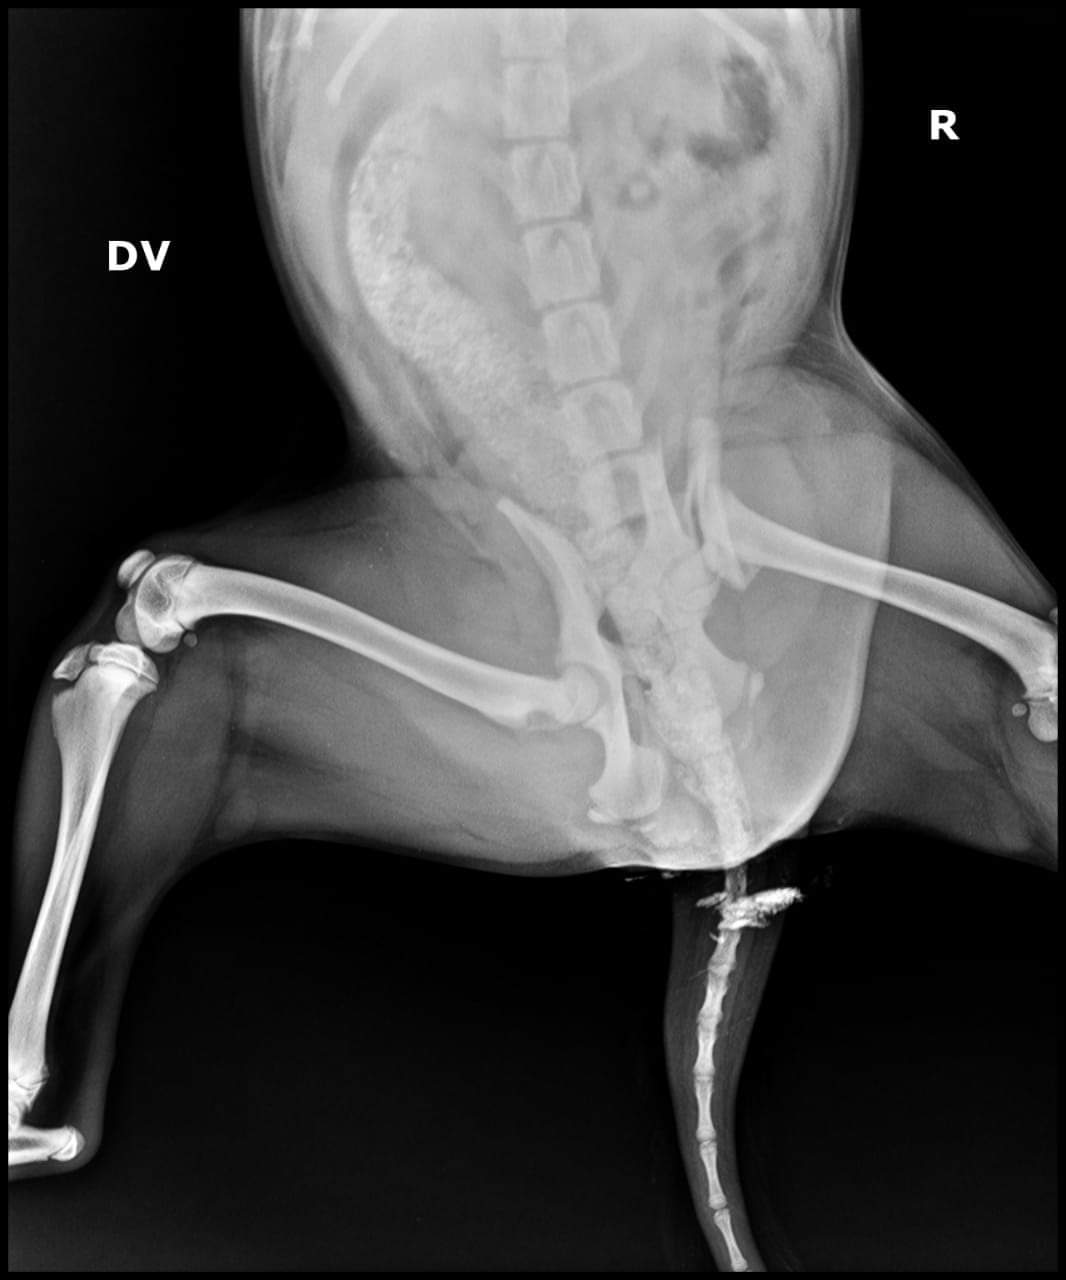

وأضافت لـ القاهرة 24: بتوقيع الكشف الطبي عليه وإجراء الأشعة اللازمة، تبين أنه مصاب بكسر في الحوض وعظمة الفخذ، ليحتاج إلى إجراء عمليتين جراحتين.